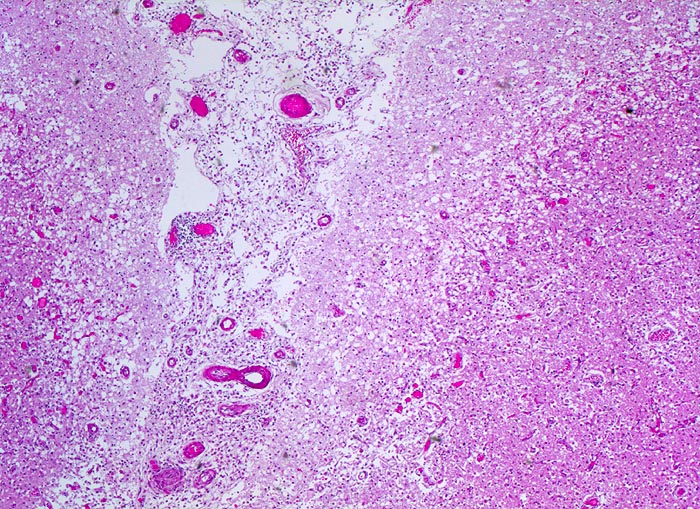

PathoPic – image database / PathoPic ID 3523 - subakuter anämischer Hirninfarkt

subakuter anämischer Hirninfarkt

Spongiotische (=Ödem) Auflockerung der Hirnrinde (hellere Areale), Gefässneubildungen und Gefässhyperämie (hämorrhagischer Randsaum) im Randbereich der Nekrose mit unscharfer Mark-Rinden Grenze. Die Hirnhaut zwischen den beiden Windungen ist entzündlich infiltriert und enthält teilweise thrombosierte Gefässe.

Vor 7 Tagen Entwicklung eines Hemisyndrom links.

Anämische Hirninfarkte entstehen als Folge eines thrombotischen oder embolischen arteriellen Verschlusses. Es kommt zur lokalen Ischämie mit Blutleere (Entfärbung des Versorgungsgebietes = weisse Enzephalomalazie) im Versorgungsgebiet der verschlossenen Arterie. Meist entsteht eine Kolliquationsnekrose (gelb-weißes Zentrum, hämorrhagischer Randsaum).